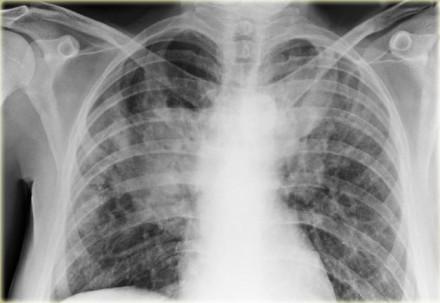

Researchers looked at a large multicentre cohort study of community-dwelling adults and examined the association of computed tomography measures of pericardial, abdominal visceral, and abdominal subcutaneous adipose tissue with high-attenuation areas (HAAs) and interstitial lung abnormalities (ILAs). They also assessed the relationship of adipose depot size with FVC and biomarkers of obesity and inflammation.

In multivariable regression models, every doubling in pericardial adipose tissue volume contributed to a 63.4-unit increase in HAA (95 percent confidence interval [CI], 55.5–71.3), 20-percent greater odds of ILA (95 percent CI, –2 to 50), and a 5.5-percent reduction in percent predicted FVC (95 percent CI, –6.8 to –4.3). Interleukin (IL)-6 levels accounted for 8 percent of the association between pericardial adipose tissue and HAA.

Meanwhile, every doubling in visceral adipose tissue area correlated with a 41.5-unit increase in HAA (95 percent CI, 28.3–54.7), 30-percent greater odds of ILA (95 percent CI, –10 to 80), and a 5.4-percent reduction in percent predicted FVC (95 percent CI, –6.6 to –4.3). IL-6 and leptin accounted for 17 percent and 18 percent, respectively, of the association between visceral adipose tissue and HAA.